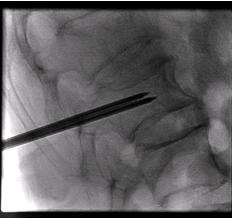

患者俯臥於X光透視檢查台上,醫師利用X光透視導引,在皮膚上施打局部麻藥後,精確的將穿刺針插入脊椎體中,再注入骨泥,注入骨泥時,醫師會一直用透視X光觀察骨泥的流動情形,以避免骨泥流入危險區域。骨泥施打完畢後,等待數分鐘,骨泥完全固化後,將穿刺針取出,傷口紗布覆蓋包紮後即完成治療。

| 顯示出穿刺針置入脊椎體 的X光片 |